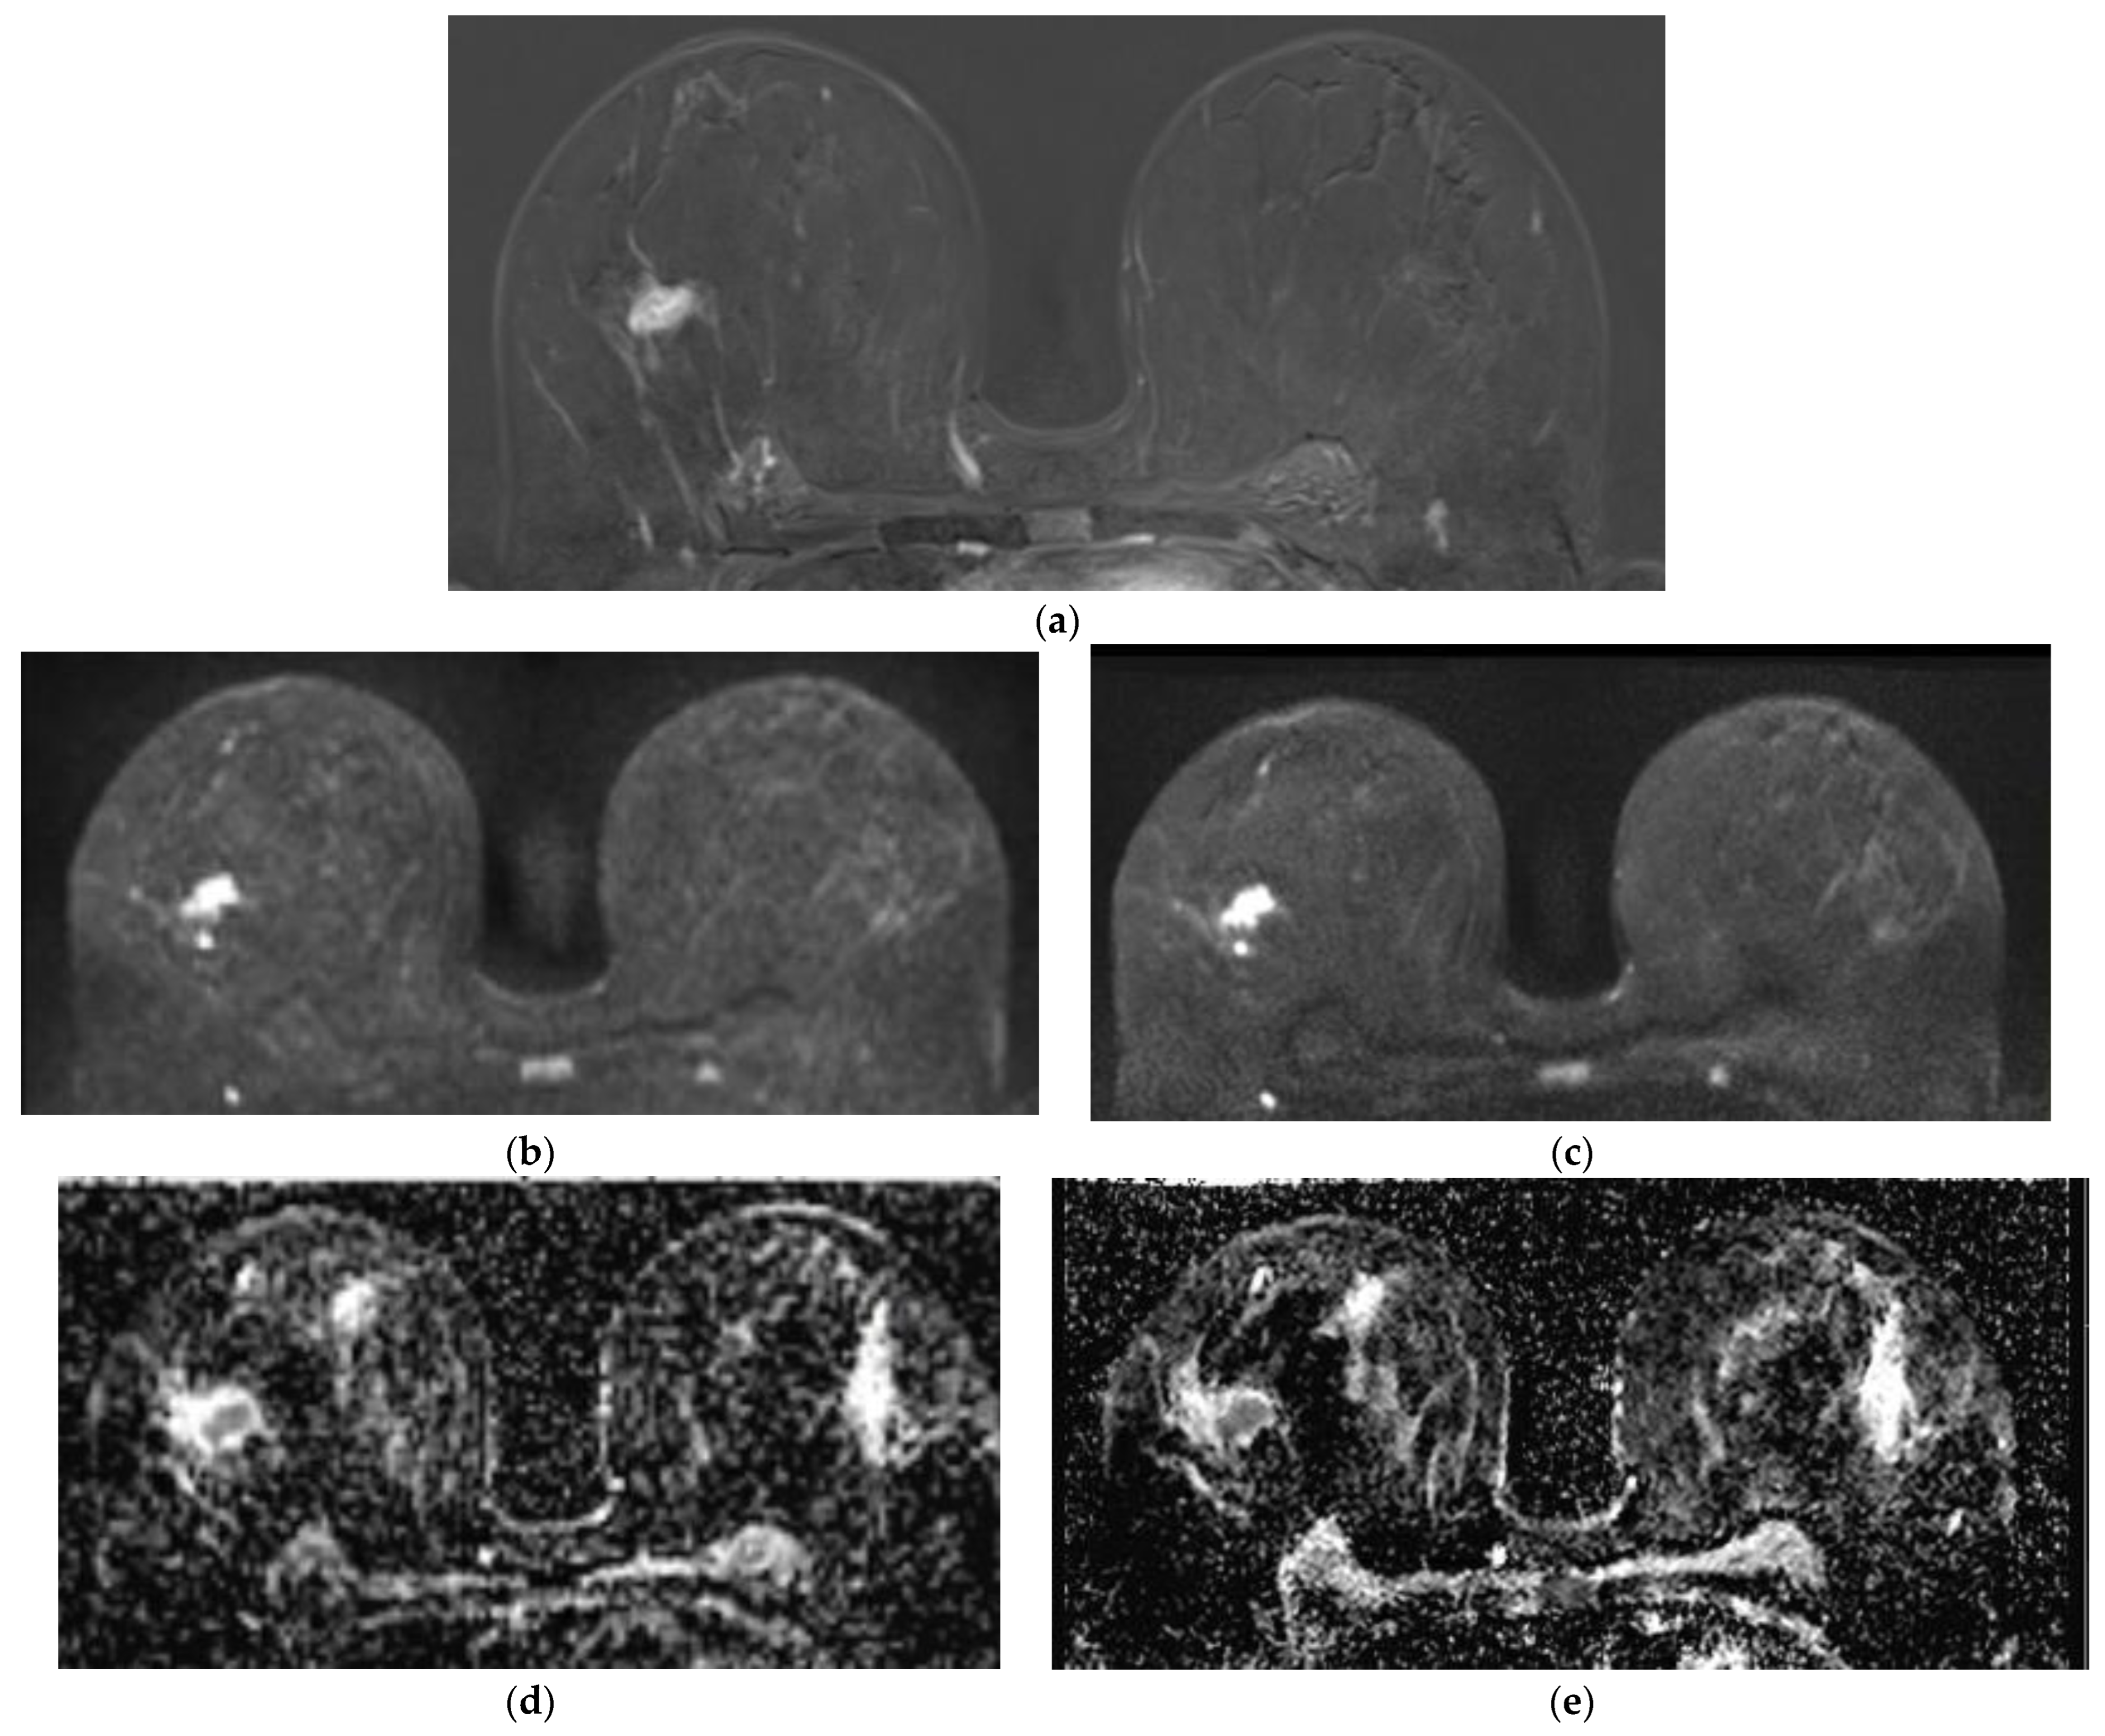

Qualitative Image Evaluation for DWI

Qualitative Image Evaluation for ADC

Lesion Visibility and Diameter